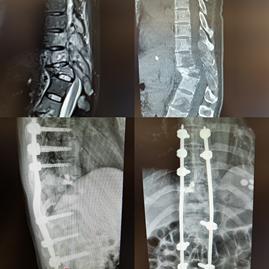

罗湖中医院(上海中医院大学深圳医院) 脊柱骨科-骨质疏松与骨肿瘤专科熟悉各类骨肿瘤疾病的诊断及治疗,对脊柱肿瘤、各类骨肿瘤的治疗有丰富的经验。

椎管内肿瘤

脊柱转移瘤

尤文氏肉瘤新辅助化疗后的保肢手术

骨巨细胞瘤(Capamnacci III级)复发肿瘤假体置换术